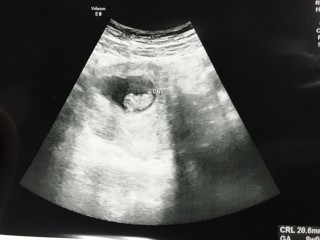

前回より約1cmも大きくなっていて18.9mm。週数通り。心臓も元気に動いていました(^^)

2人目です。最終生理日からだと8w5dですが大きさは9w2dとちょっぴり気持ち大きいようです!お腹の中で、元気いっばい成長してもらいたいです。